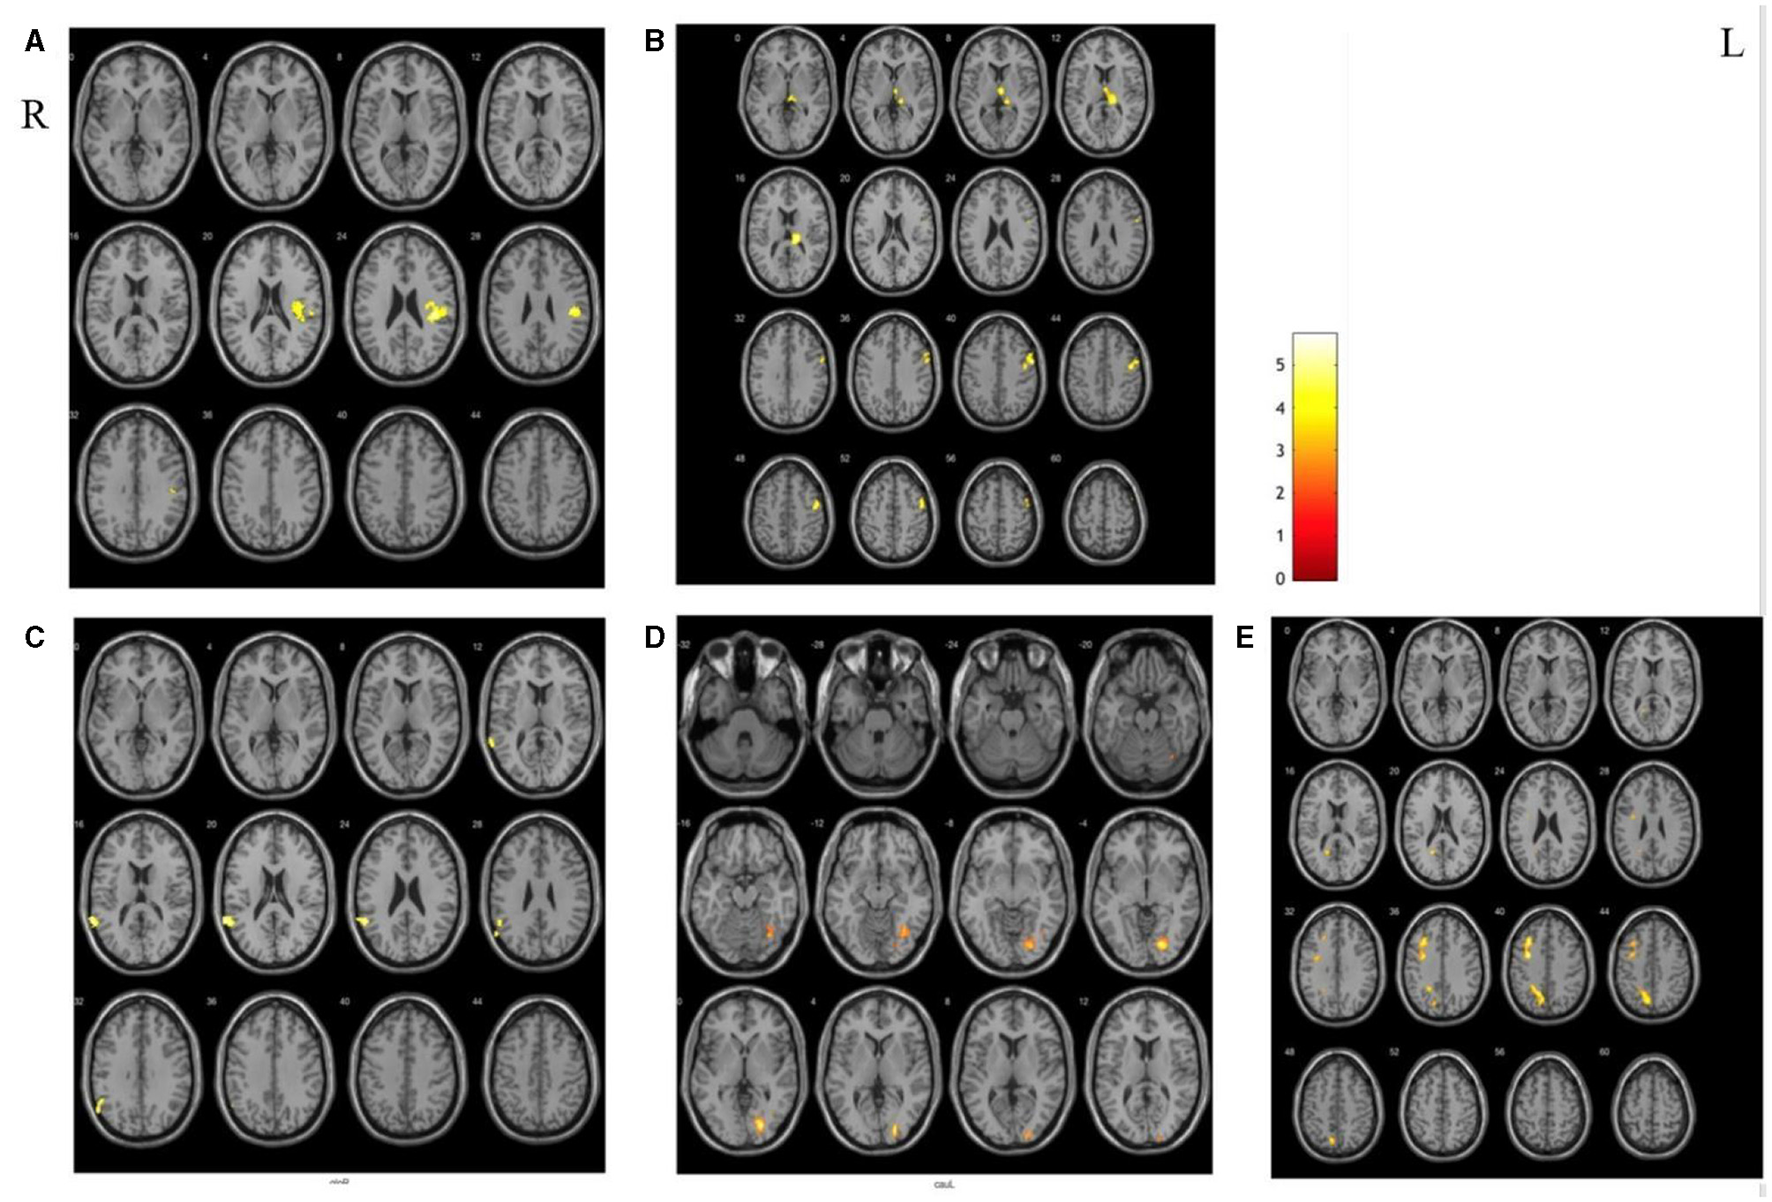

RSFC between SAs and PCs

Compared with the PCs, there were significant differences in extensive brain regions of RSFC in SAs after treatment, and their localizations were as follows: (a) increased RSFC of the right putamen with the right posterior central gyrus and insula; (b) increased RSFC of the left thalamus with the right thalamus, the occipital thalamus, and the precentral gyrus; (c) decreased RSFC of the left globus pallidus with the left superior temporal gyrus; (d) decreased RSFC of the left caudate nucleus with the right lingual gyrus; (e) decreased RSFC of the left thalamus with the left middle frontal gyrus and precuneus (Figure 4).

Figure 4

The different areas of functional connectivity between SAs and PCs after treatment. (A, B) Increased RSFC between SAs and PCs; (C–E) deceased RSFC between SAs and PCs.